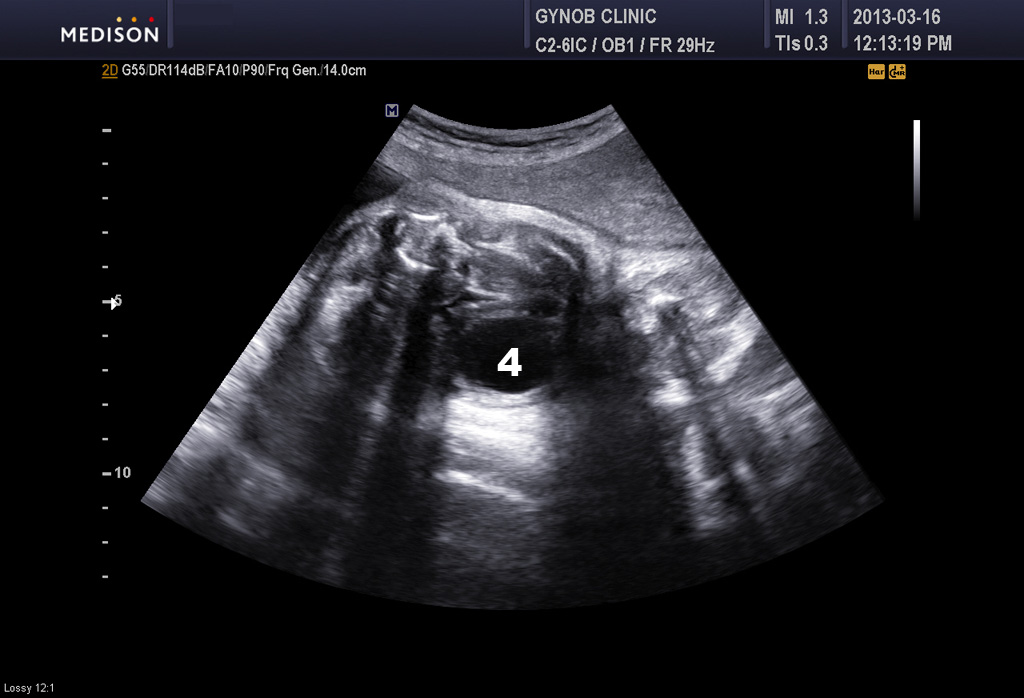

아래 사진은 본원에서 찍은 초음파 사진으로 콩팥과 방광의 정상 모습입니다.

1번과 2번은 좌우측 콩팥이며 3번은 척추 4번은 방광입니다.